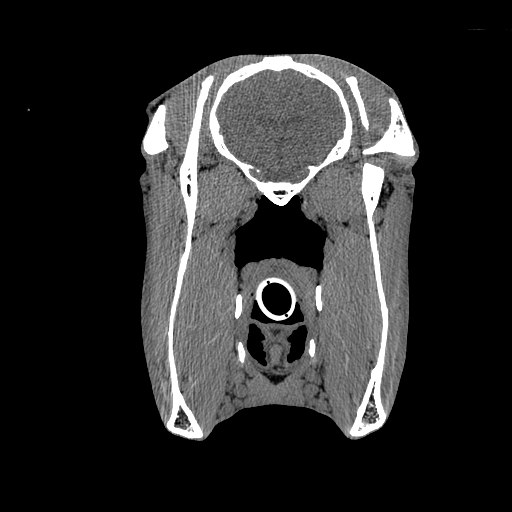

VetTom 8 provides diagnostic quality Computed Tomography (CT) images in a small mobile package. The system is capable of providing at 25 cm field-of-view with high contrast to noise giving you diagnostic confidence for soft-tissue disease and injury.

The modern Through-Silicon-Via (TSV) stacked CT detectors provide high-resolution images with low noise and high contrast, while the 40 cm gantry and 30 cm field-of-view provide additional space and information for your diagnostic needs versus VetTom 8.

The VetTom 32 has a powerful 40 kW generator, 85 cm gantry, 60 cm field-of-view, scans using proprietary batteries and can be moved to where you need imaging, especially when it may be difficult to move the patient.